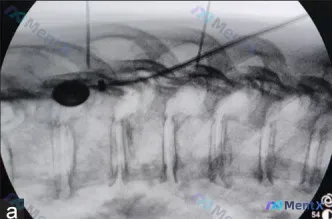

整理到一张脊柱微创介入的术中C臂透视影像(胸椎侧位),先不说结论,大家看看: - 图像左侧可见一个椭圆形透亮区 - 有细长线性穿刺针/导丝影穿入目标椎体 - 目前未见明确的高密度骨水泥影 单从这一帧侧位片,你第一眼会往哪个方向想? 另外提醒一下:这张图是治疗过程记录,不是术前诊断片,但即使是术中,也...